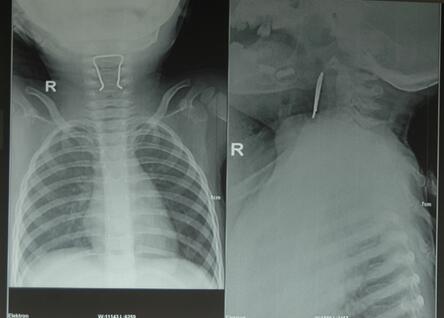

2月4日上午12点08分河池市保平乡一位1岁6个月的患儿误吞金属异物后,吞咽困难2小时,生命垂危,被父母送进我院耳鼻喉科门诊急救。经检查口咽部未见异物,急送放射科进行胸正侧位照片,发现食道入口处可见“U”型金属异物,诊断为食道异物。当时已超过下班时间十多分钟,时间就是生命,耳鼻喉科主任、主治医师韦善文急病人之所急、想病人之所想,与放射科主治医师胡琪琳配合在无麻醉下,不到2分钟时间采用异物钳把金属异物取出。